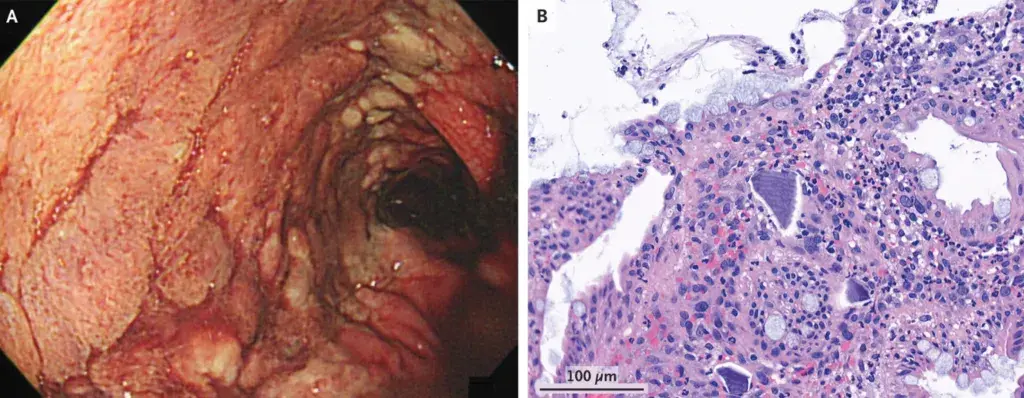

Caso clínico muito interessante publicado no NEJM ([link](https://www.nejm.org/doi/full/10.1056/NEJMicm2205643?query=featured_nephrology)), trata-se de um paciente em tratamento de hipercalemia com poliestirenossulfonato de cálcio por 06 dias. Paciente evoluiu com dor abdominal e sangramento intestinal. Realizado colonoscopia que revelou uma úlcera contínua com extensão da flexura esplênica até o reto (Painel A). Biópsia da mucosa colônica mostrou lesão epitelial e cristais basofílicos de poliestirenossulfonato de cálcio em um fundo necroinflamatório (Painel B). Foi feito o diagnóstico de necrose colônica relacionada ao poliestireno sulfonato de cálcio. Em raros casos pode ocorrer lesão gastrointestinal com o uso de sulfonato de poliestireno de cálcio ou seu análogo, sulfonato de poliestireno de sódio, logo devemos ser bem cuidadosos quando indicarmos tratamento prolongado com resinas de troca.